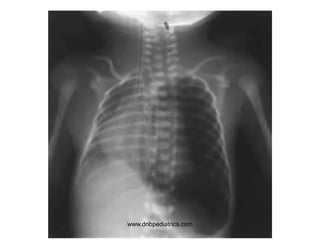

3 day neonate with

• Lethargy

• Feed refusal

• Abdominal

distension

1. What stage of NEC is depicted in the

X-ray?

2. What is the radiological feature of Bell

stage III NEC?

3. Name two more conditions associated

with pneumatosis intestinalis?

1. NEC Stage II

2. Pneumoperitoneum

3. Any two of following

Hirschsprung's

disease, Pseudomembranous

enterocolitis, Neonatal ulcerative colitis,

Ischemic bowel disease